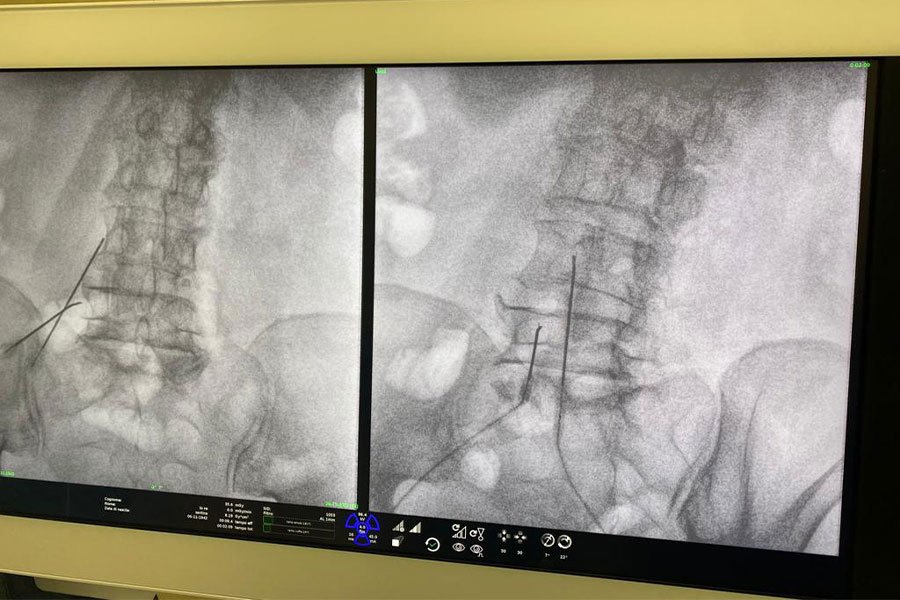

È una tecnica percutanea che, sotto guida radiologica o ecografica ed in anestesia locale, prevede l’introduzione di un ago in corrispondenza dei rami nervosi che vengono sottoposti a stimolazione con impulsi elettrici, non percepiti dal paziente, che mirano a neuromodulare la conduzione dolorosa. La procedura, in regime di day surgery, viene eseguita in sala operatoria, è priva di effetti avversi e può portare ad un beneficio duraturo con scomparsa o riduzione della sintomatologia dolorosa per diversi mesi.